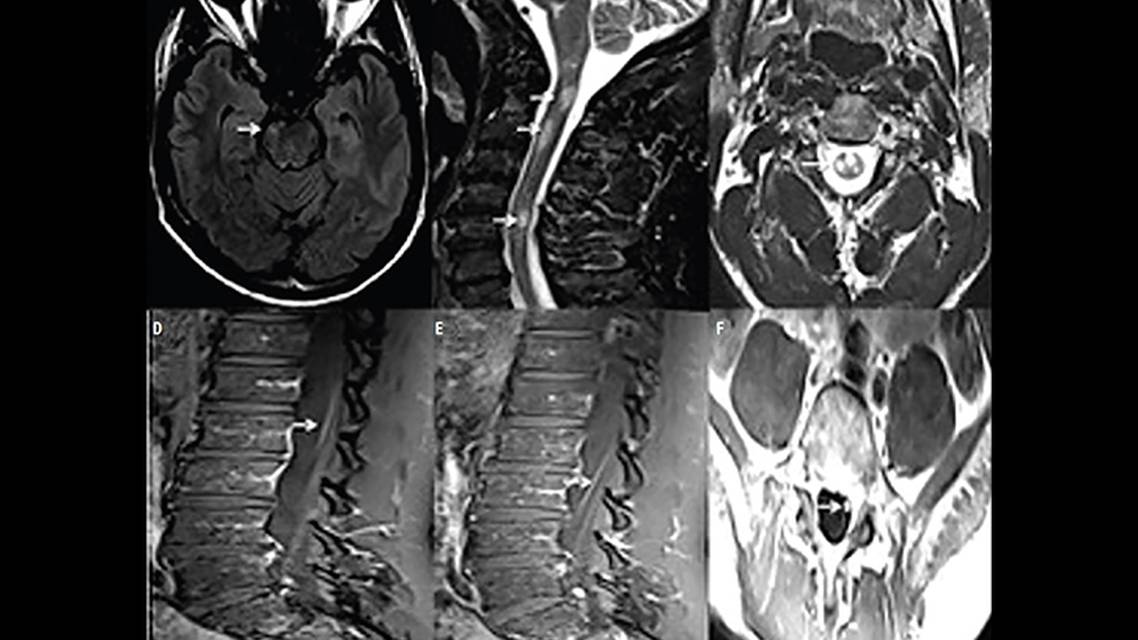

Cervical, thoracic, and lumbar spine MRI with and without contrast revealed multifocal short-segment T2 hyperintense lesions, diffusely central in location and involving both gray and white matter (Figure). None of the lesions were longitudinally extensive, although some showed trace areas of contrast enhancement. Enhancement in the cauda equina nerve roots and focal lobular enhancement of the left S1 nerve root was observed. Brain MRI showed several small T2-hyperintense brainstem lesions, none of which displayed contrast enhancement. These radiologic findings were most consistent with an acute or subacute inflammatory process.

Associated spinal cord lesions are often multifocal because MOGAD tends to simultaneously affect multiple areas of the central nervous system (CNS),6 as was the case for WN. Although LETM is more common, short segment transverse myelitis is seen in up to 40% of cases.8 Radiologic signs that can help distinguish MOGAD-associated myelitis from other inflammatory myelitides include minimal or lack of contrast enhancement and longitudinally extensive T2 signal abnormality confined to gray matter, resulting in a T2 hyperintense line on the sagittal view and an “H sign” on the axial view.9